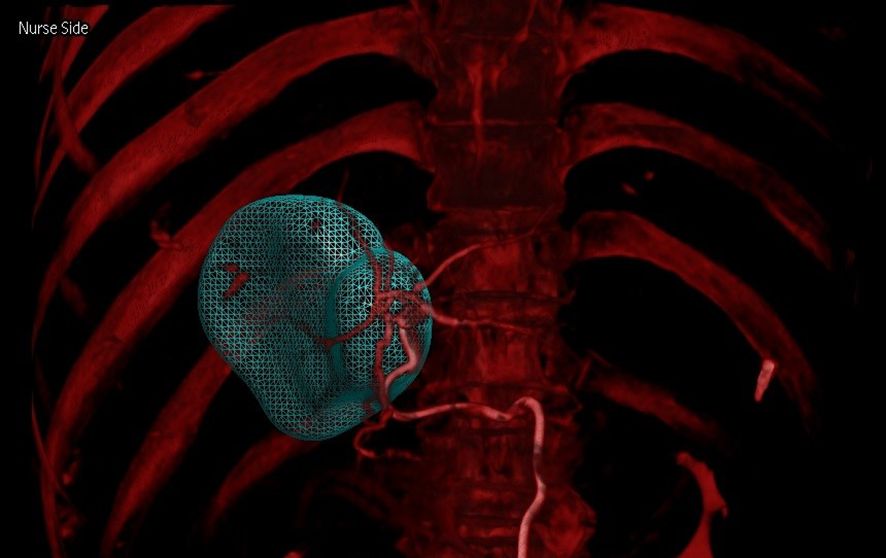

Figure 5

CT scan showing a 3D rendering of a human thorax in red, with a teal mesh structure highlighting an area within the chest cavity.

Figure 5. Combining arterial and venous phase CBCT imaging (dual CBCT-overlay image) enables rapid and accurate identification of tumor-supplying arteries, facilitating more precise 90Y therapy delivery.

3.4 Optimizing tumor-feeding artery identification and catheter insertion

This study utilized dual CBCT technology to precisely locate tumors and their feeding vessels. Figure 6 and Figure 7 showed dual CBCT from the same cross-section obtained after super-selection, used to construct a 3D reconstruction model of the tumor and its blood supply vessels. The 3D model, viewed from a left anterior oblique position, clearly displays the spatial relationships between the tumor and its vessels. This detailed reconstruction significantly enhanced the precision and effectiveness of subsequent interventional procedures. Figure 8 illustrated the confirmation process conducted via arteriography after super-selection, verifying vascular localization and providing reliable data for subsequent operations.